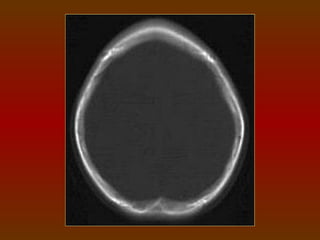

TC CRÂNIO AXIAL

COM JANELA ÓSSEA

TC CRÂNIO AXIAL COMJANELA ÓSSEA